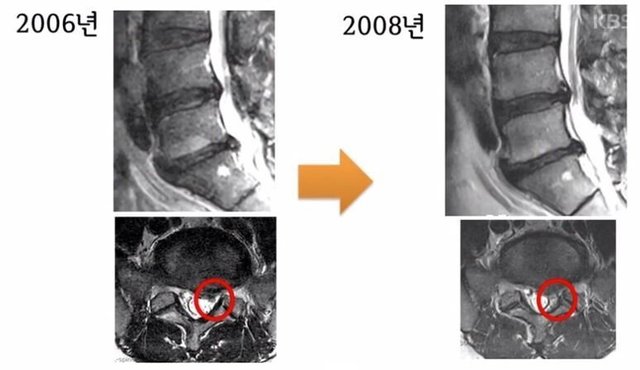

19.11.15 652 읽음 디스크와 허리 근육 강화 .jpg 푸들이곰 구독하기 0 4 콘텐츠의 수익 0 150kg 스쿼트 치던 서울대 재활의학교수님어느 날 운동하다 다리가 저리기 시작아~드디어 운동빨쫌 먹히는가 싶어서더 열심히 하는데운동 안 해도 다리가 저리기 시작mri 찍어보니 디스크 탈출이후 허리 주변 근육을 강화하는 운동을2년간 열심히 함mri 찍어보니허리 운동 전보다 디스크 더 심해짐이제는 가만히 있어도 아픈 수준이때 전문가인본인도 이러한데일반인들은 어땠을까자기가 치료한 환자들은 어땠을까라며 4 0 / 300 입력